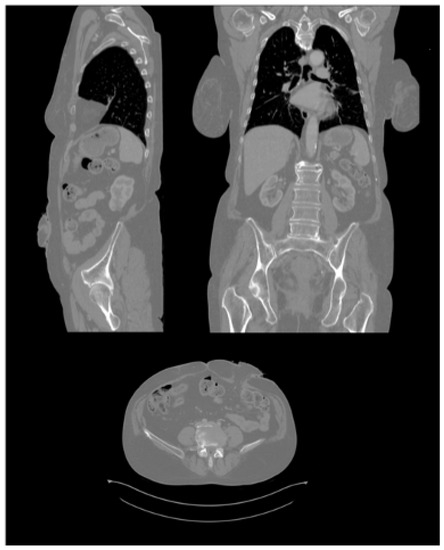

2.3.4. CT Scans

2.3.5. Processing of CT Scans and Design of the Ostomy Patch